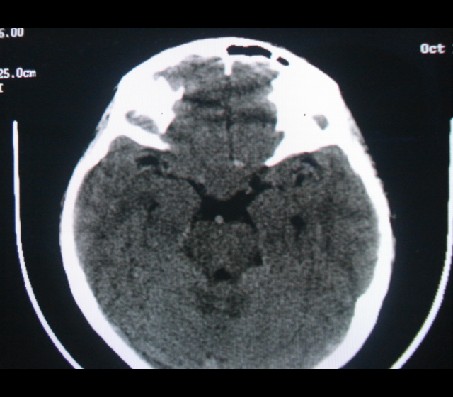

男性,12岁。反复头痛呕吐半月。脑积液无异常。病变部位ct值32hu,dwi无异常。

平扫看首先考虑颅咽管瘤,病人需增强扫描。

鞍内囊性占位性病变,t1wi、t2wi,均为高信号影。ct平扫为等密度。发病年龄较小。故首先考虑颅咽管瘤,可以做ct增强扫描